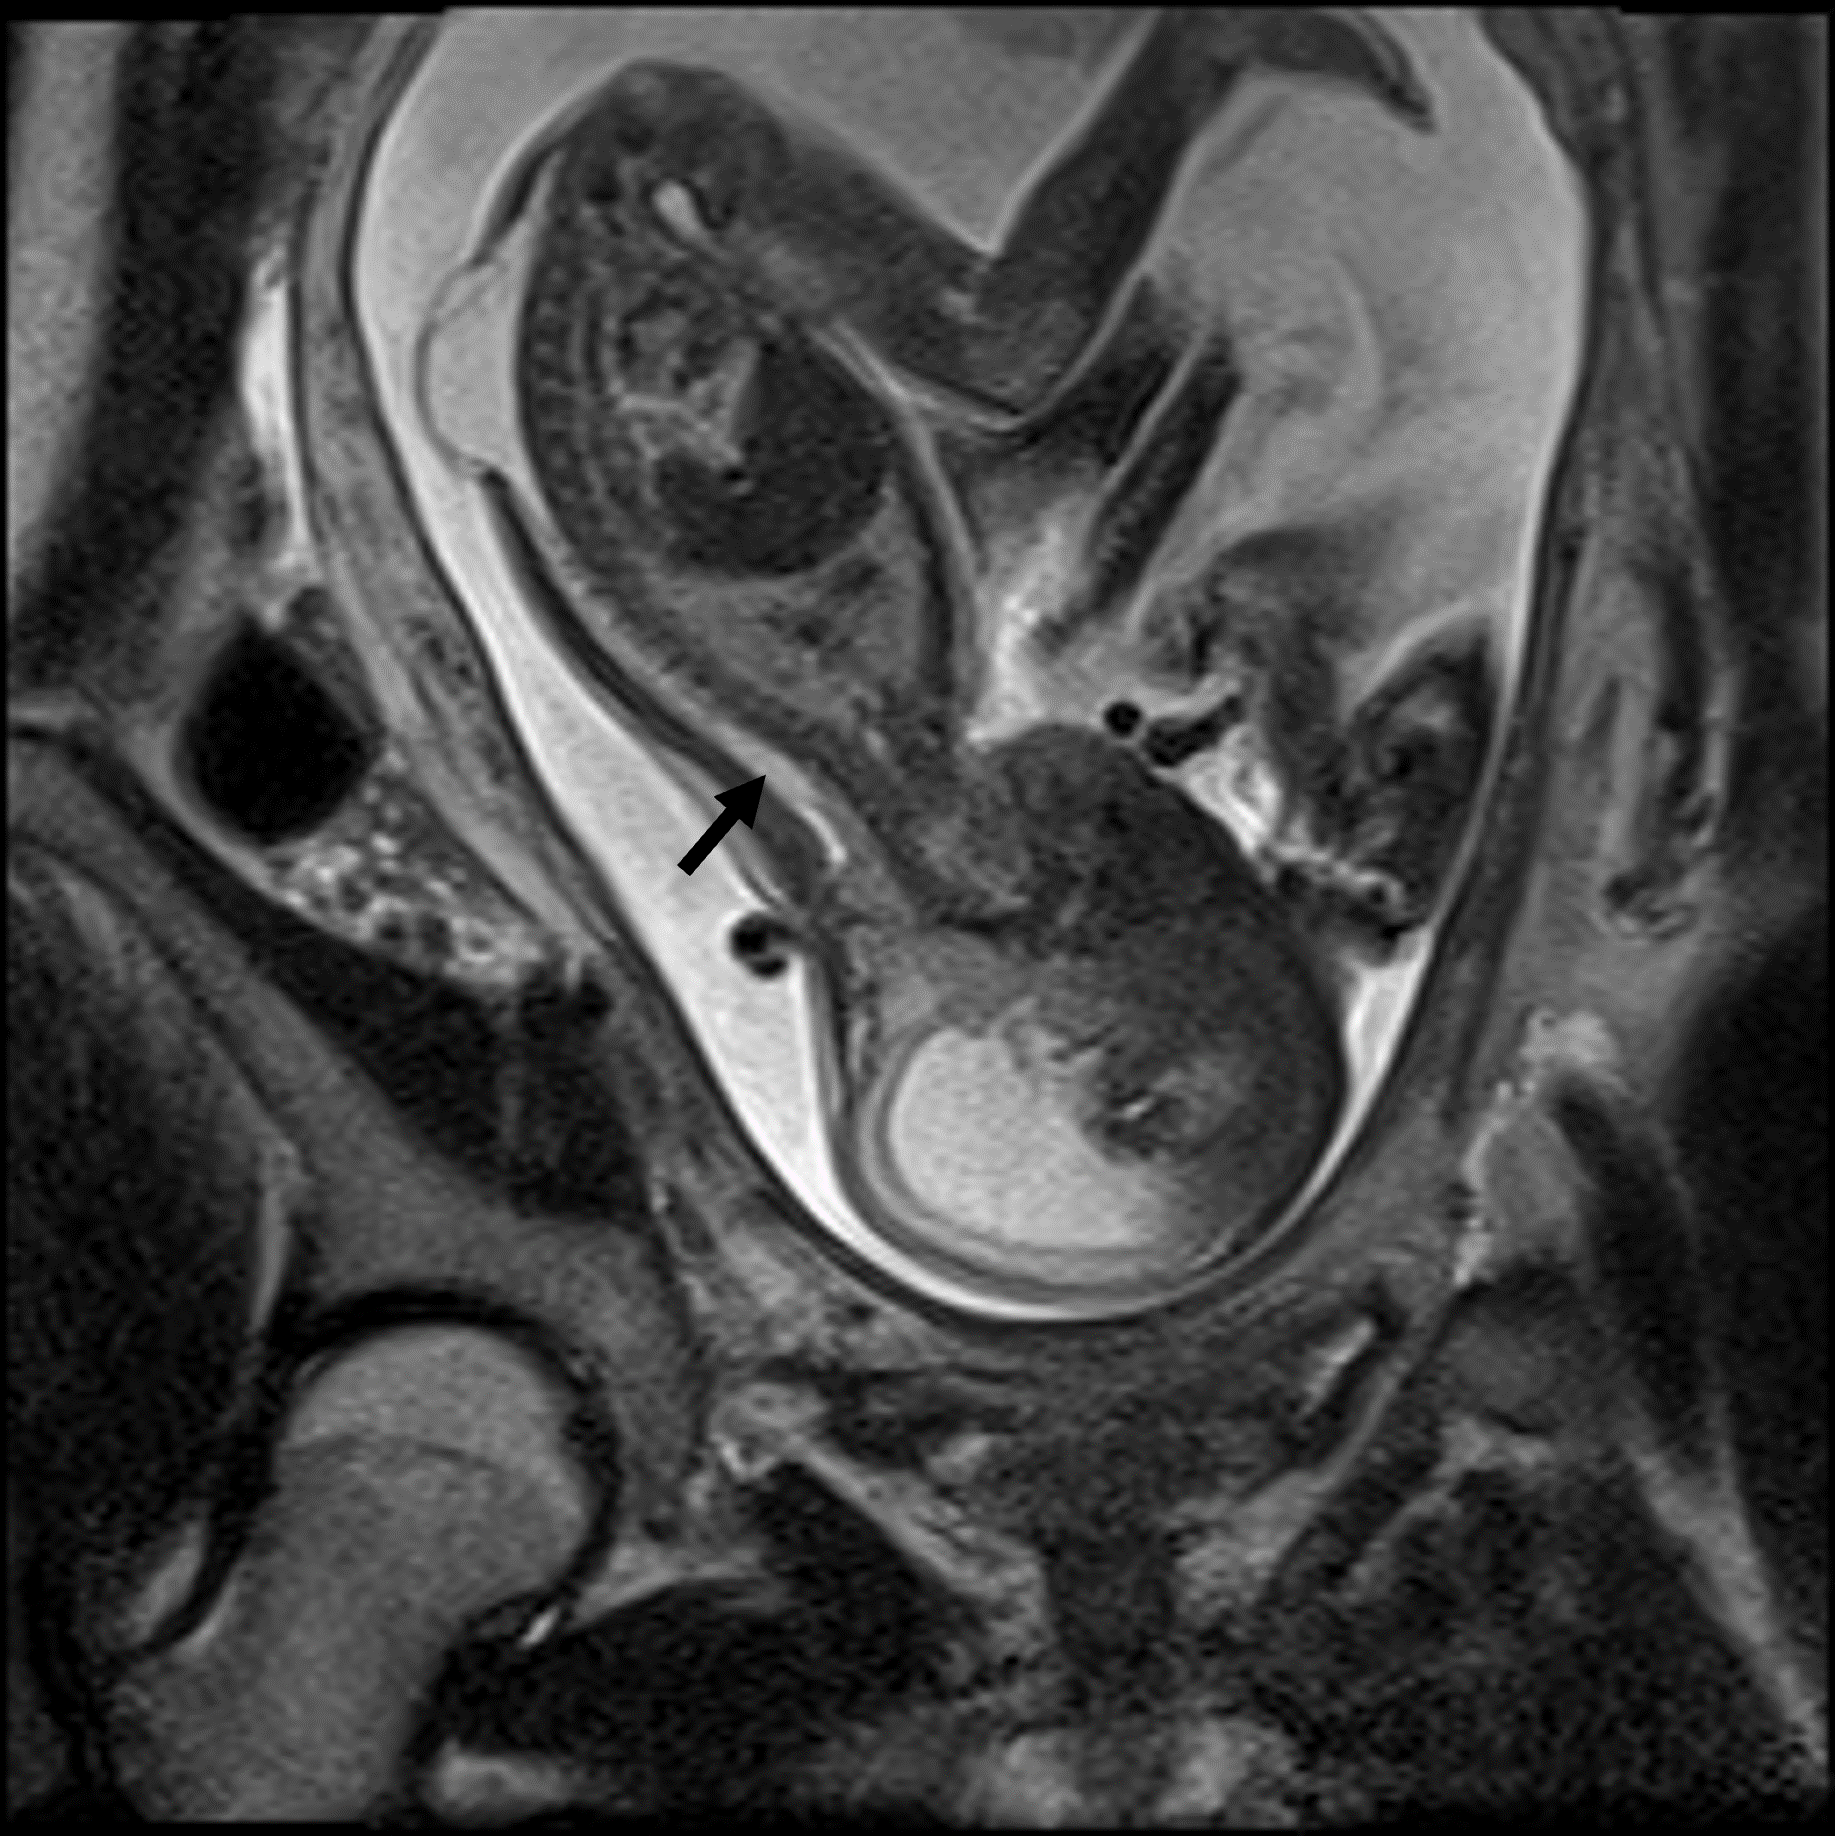

Das fetale MRT (Magnetresonanztomographie) ist ein strahlungsfreies Verfahren, mit dem wir Organe und Strukturen Ihres ungeborenen Kindes besonders detailreich darstellen. Es ergänzt die pränatale Ultraschall-Diagnostik und hilft, Fragestellungen präzise zu klären und die weitere Betreuung zu planen.

- Abklärung von Auffälligkeiten im Ultraschall, z. B. Gehirn, Wirbelsäule, Lunge, Bauchorgane

- Beurteilung von Organreife und Entwicklung, wenn die Sicht im Ultraschall eingeschränkt ist (z. B. mütterlicher Body-Mass-Index, Lage des Kindes)

- Therapieplanung vor/nach intrauterinen Eingriffen oder für die Geburt in einem spezialisierten Zentrum

Unsere Neuroradiologen arbeiten eng mit Pränatalmedizinern, Neonatologen, Pädiatern und Chirurgen zusammen. Modernste Geräte und spezialisierte Protokolle sorgen für hohe Bildqualität – auch bei kindlichen Bewegungen.